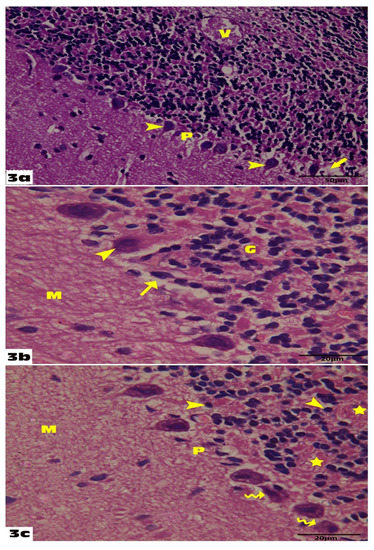

3.1. The Ameliorative Effect of Empagliflozin on Histological and Immunohistochemical Results